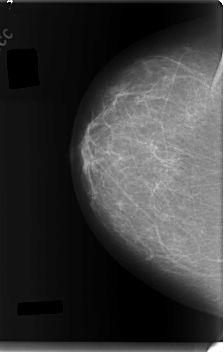

C_0116_1.RIGHT_CC

RIGHT_CC LINES 5976 PIXELS_PER_LINE 3808 BITS_PER_PIXEL 12 RESOLUTION 50 NON_OVERLAY